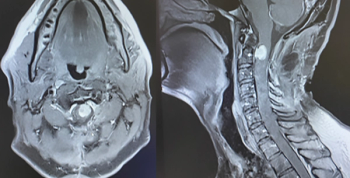

A rare case of spinal atypical teratoid/rhabdoid tumor is presented in an adult man after presenting with neck pain and bilateral upper extremity paralysis.